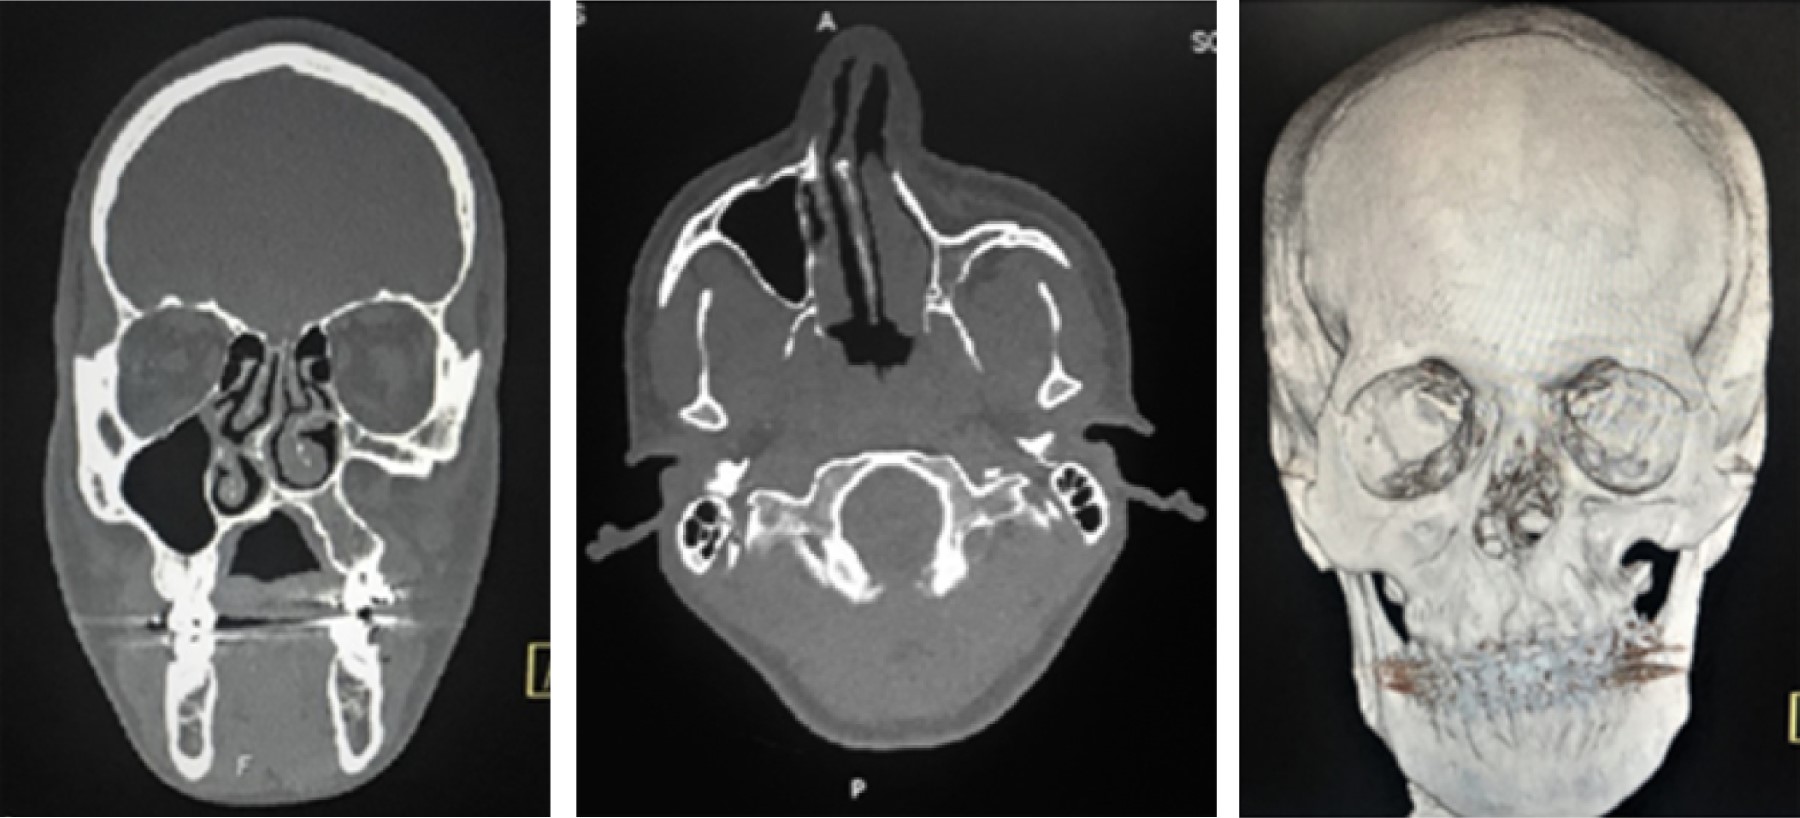

Se trata de un hombre de 18, el cual es remitido al Servicio de Cirugía Maxilofacial del Instituto Nacional de Enfermedades Respiratorias por Departamento de Ortodoncia de Clínica Dental Universitaria para valoración por asimetría facial. Se encuentra en su cuarto año de tratamiento ortodóntico con el objetivo de realizar ortodoncia camuflaje. No refiere antecedentes médicos de relevancia, incluidos antecedentes quirúrgicos o traumáticos. A la exploración física observamos paciente neurológicamente íntegro, cráneo normocefálico, adecuada inserción del cabello, presenta distopia a expensas de enoftalmos ojo izquierdo, hipoplasia fosa nasal y pabellón auricular izquierdo, depresión en región infraorbitaria ipsilateral (Figura 1) perfil cóncavo clase III, canteamiento maxilar, sin alteraciones en región de ATM con adecuados movimientos mandibulares, intraoralmente con mal oclusión clase III de Angle, sobremordida negativa y mala posición dental. Se solicita tomografía computarizada con cortes finos y ventana para hueso, observando en los cortes coronales un aumento en el volumen de la órbita izquierda, así como ausencia completa del seno maxilar izquierdo, desviación del septum nasal e hiperplasia de cornete inferior izquierdo, en los cortes axiales se corrobora aplasia de seno maxilar izquierdo y en reconstrucción 3d se observa en la vista anterior una depresión de la pared anterior del hueso maxilar (Figura 2). El plan de tratamiento propuesto es la toma y aplicación de injerto autólogo de cresta iliaca anterior para corregir la pérdida de volumen en la región anterior del maxilar y cirugía ortognática para corregir la discrepancia dentoesqueletal.

Figura 2